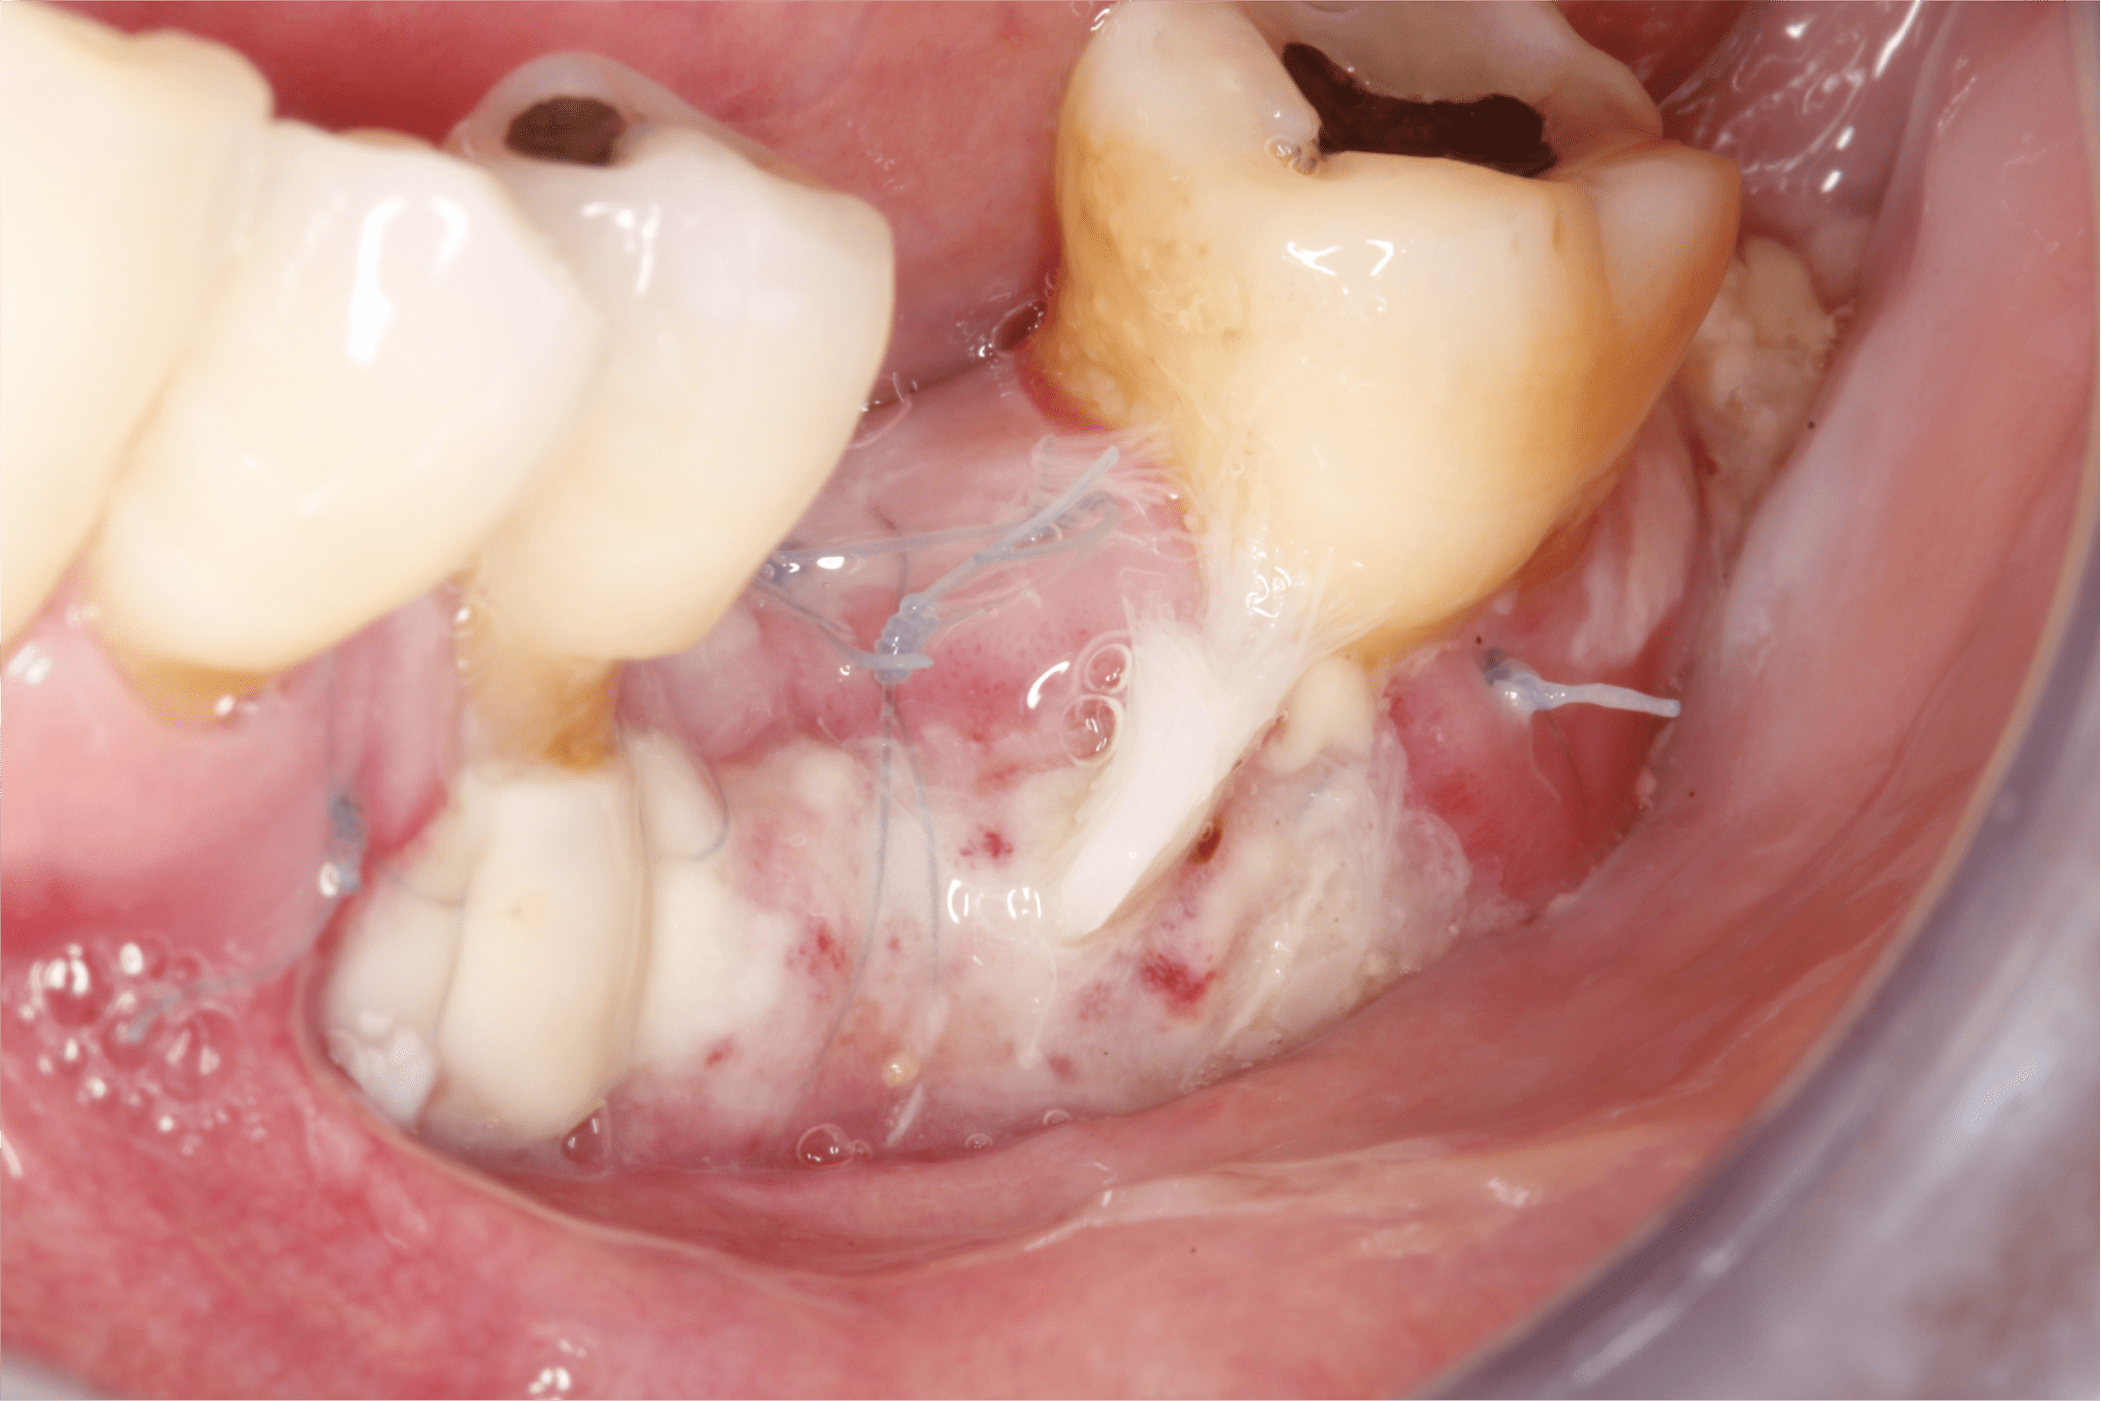

Una vez tomado el injerto epitelial se posicionó en el sitio receptor previamente preparado, se fijó con puntos simples en sus extremos y en la porción media se fijó con puntos colchoneros horizontal y cruzado (Fig. 9 y 10).

Fig. 9

Fig. 10